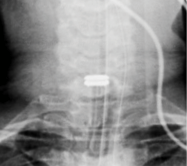

The patient was found to have multiple levels of degenerative disc disease with the highest degree of stenosis at C6-7 which showed moderate central canal stenosis, severe left foraminal stenosis, and moderate right foraminal stenosis. There is posterior element buckling at C6-7, indicative of loss of height of the functional spinal unit.

There was slight retrolisthesis without any motion on flexion-extension at C6-7.

Radiographs and computed tomography demonstrate early formation of a ventral osteophyte without any significant foraminal or canal osteophytes.

prodisc C Vivo implanted: 17x14x5mm